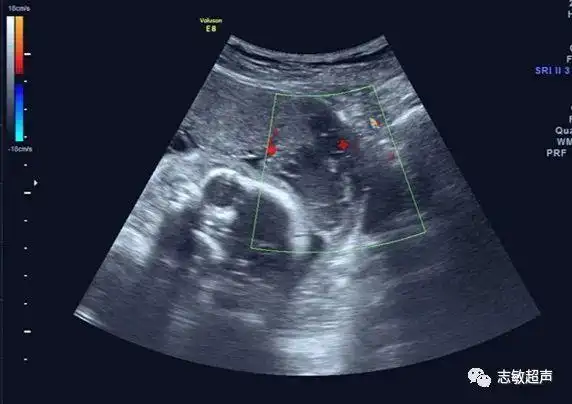

胎盘的下缘为血窦时